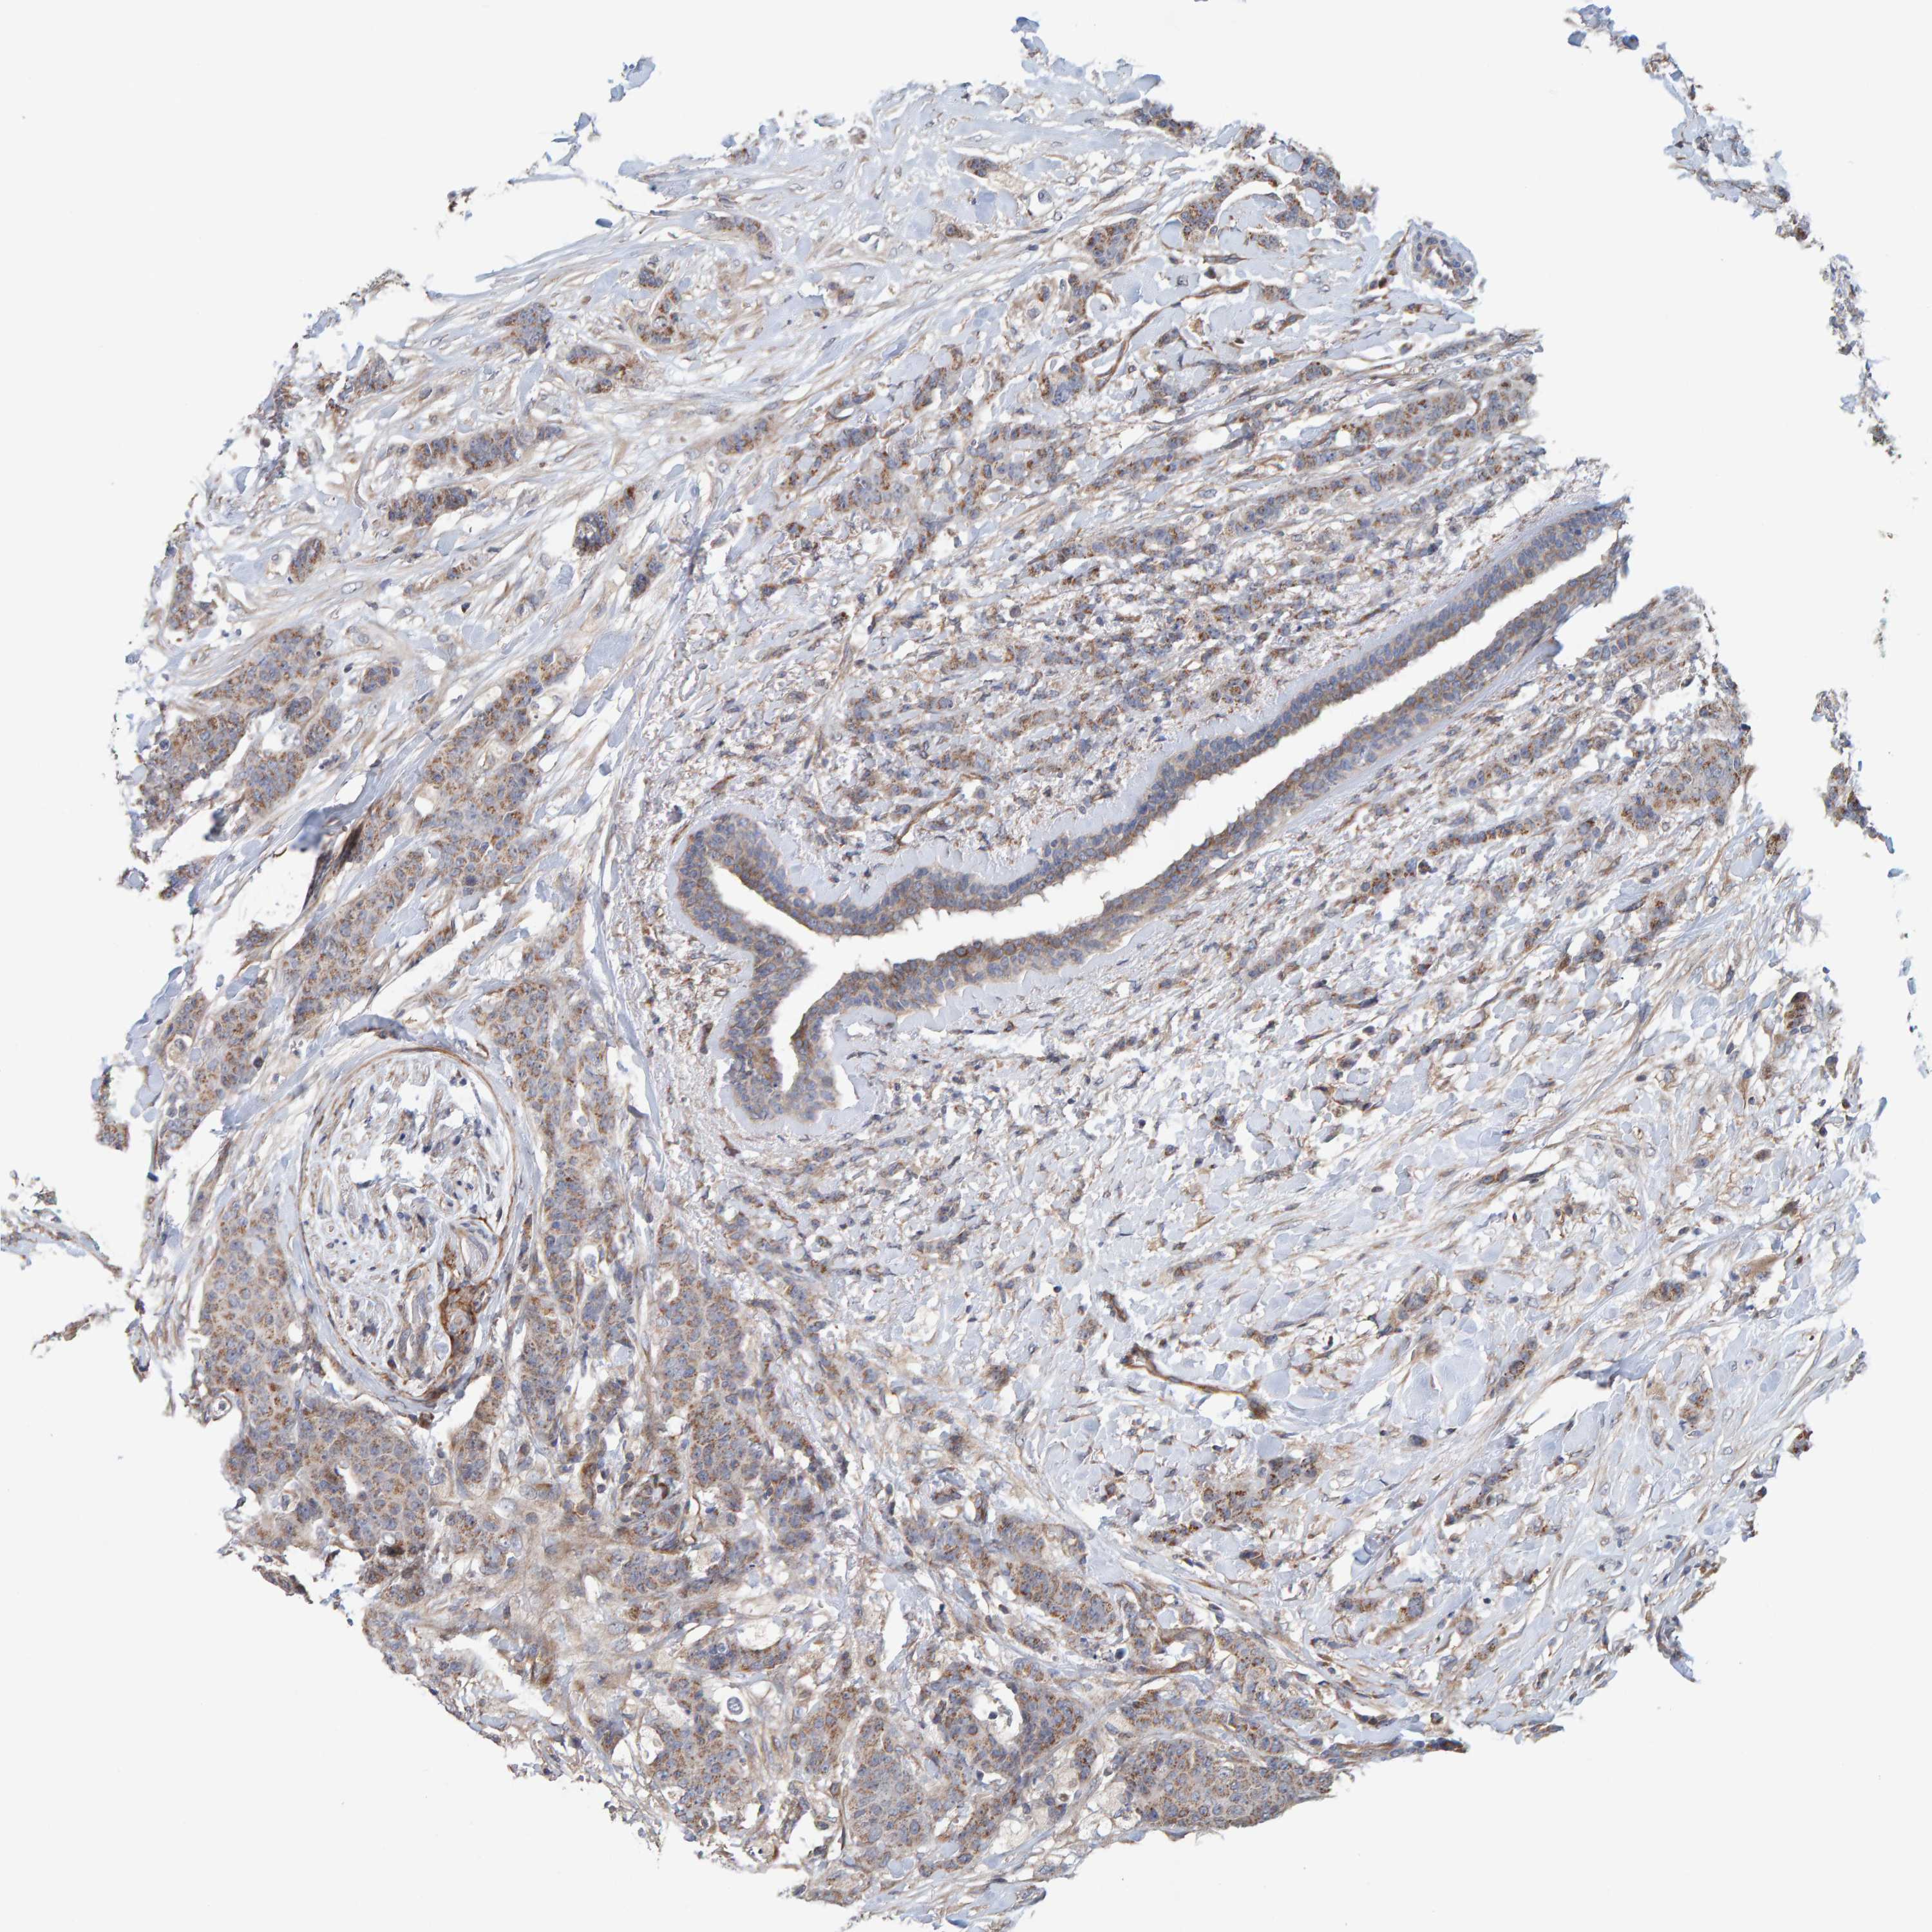

CANCER BREAST CANCER Show tissue menu

BRCA TCGA BRCA VALIDATION PROTEIN EXPRESSION

ANTIBODIES

AND

VALIDATION